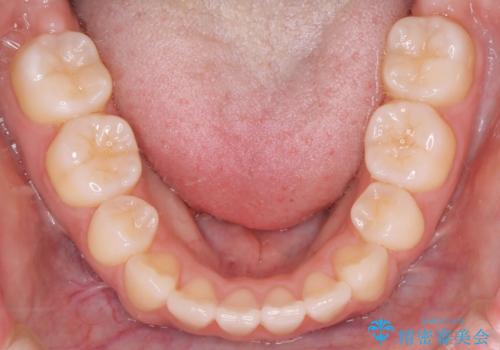

【ワイヤー矯正】オープンバイトを治したい

- 4番の歯を4本抜歯をし、上顎にマイクロインプラントを2本埋入し、遠心移動を行いました。

主訴のオープンバイトは改善し、抜歯をしたことで前歯が下がり綺麗になりました。抜歯矯正でしたが1年2か月という短い期間で終了しました。